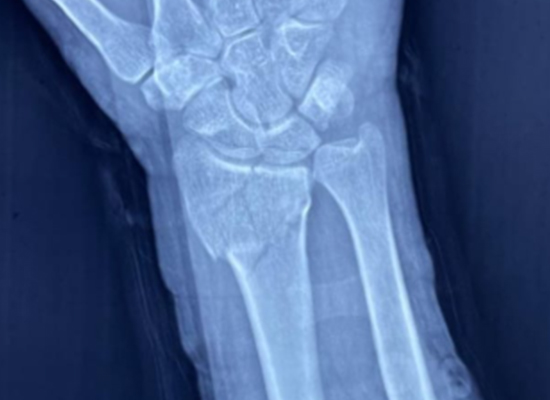

A 53-year-old patient sustained a radius fracture near the wrist after a fall. The medical team opted for internal fixation using a variable angle distal radius locking plate, ensuring anatomical reduction and early mobilization.

This case demonstrates how locking plate fixation can restore joint stability and function, especially in complex intra-articular fractures of the distal radius.